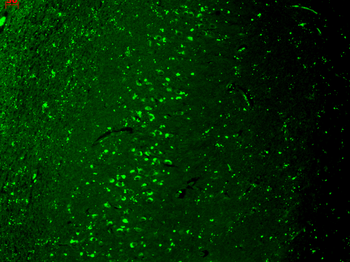

Immunohistochemical staining of human colon cancer using TRPV1 antibody